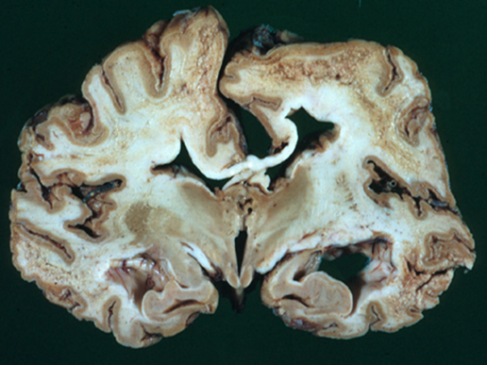

Biochemical defect- A prion is a protein type that can trigger normal proteins (PrPC) in the brain to fold abnormally. The normal function of this protein is unknown. The prion protein binds with a normal protein to alter its structure and, thus, functions. Misfolded proteins ((PrPSc) accumulate to form clumps in the brain, damaging the brain cells. The damaged brain gives a spongiform appearance under a microscope. Due to this characteristic, Prion disease is also called “Spongiform encephalopathy” (figure 3)

Figure-3- A) Showing the transformation of a normal protein to a Prion protein (PrPSc) and B) Spongiform appearance of the brain in Prion disease.